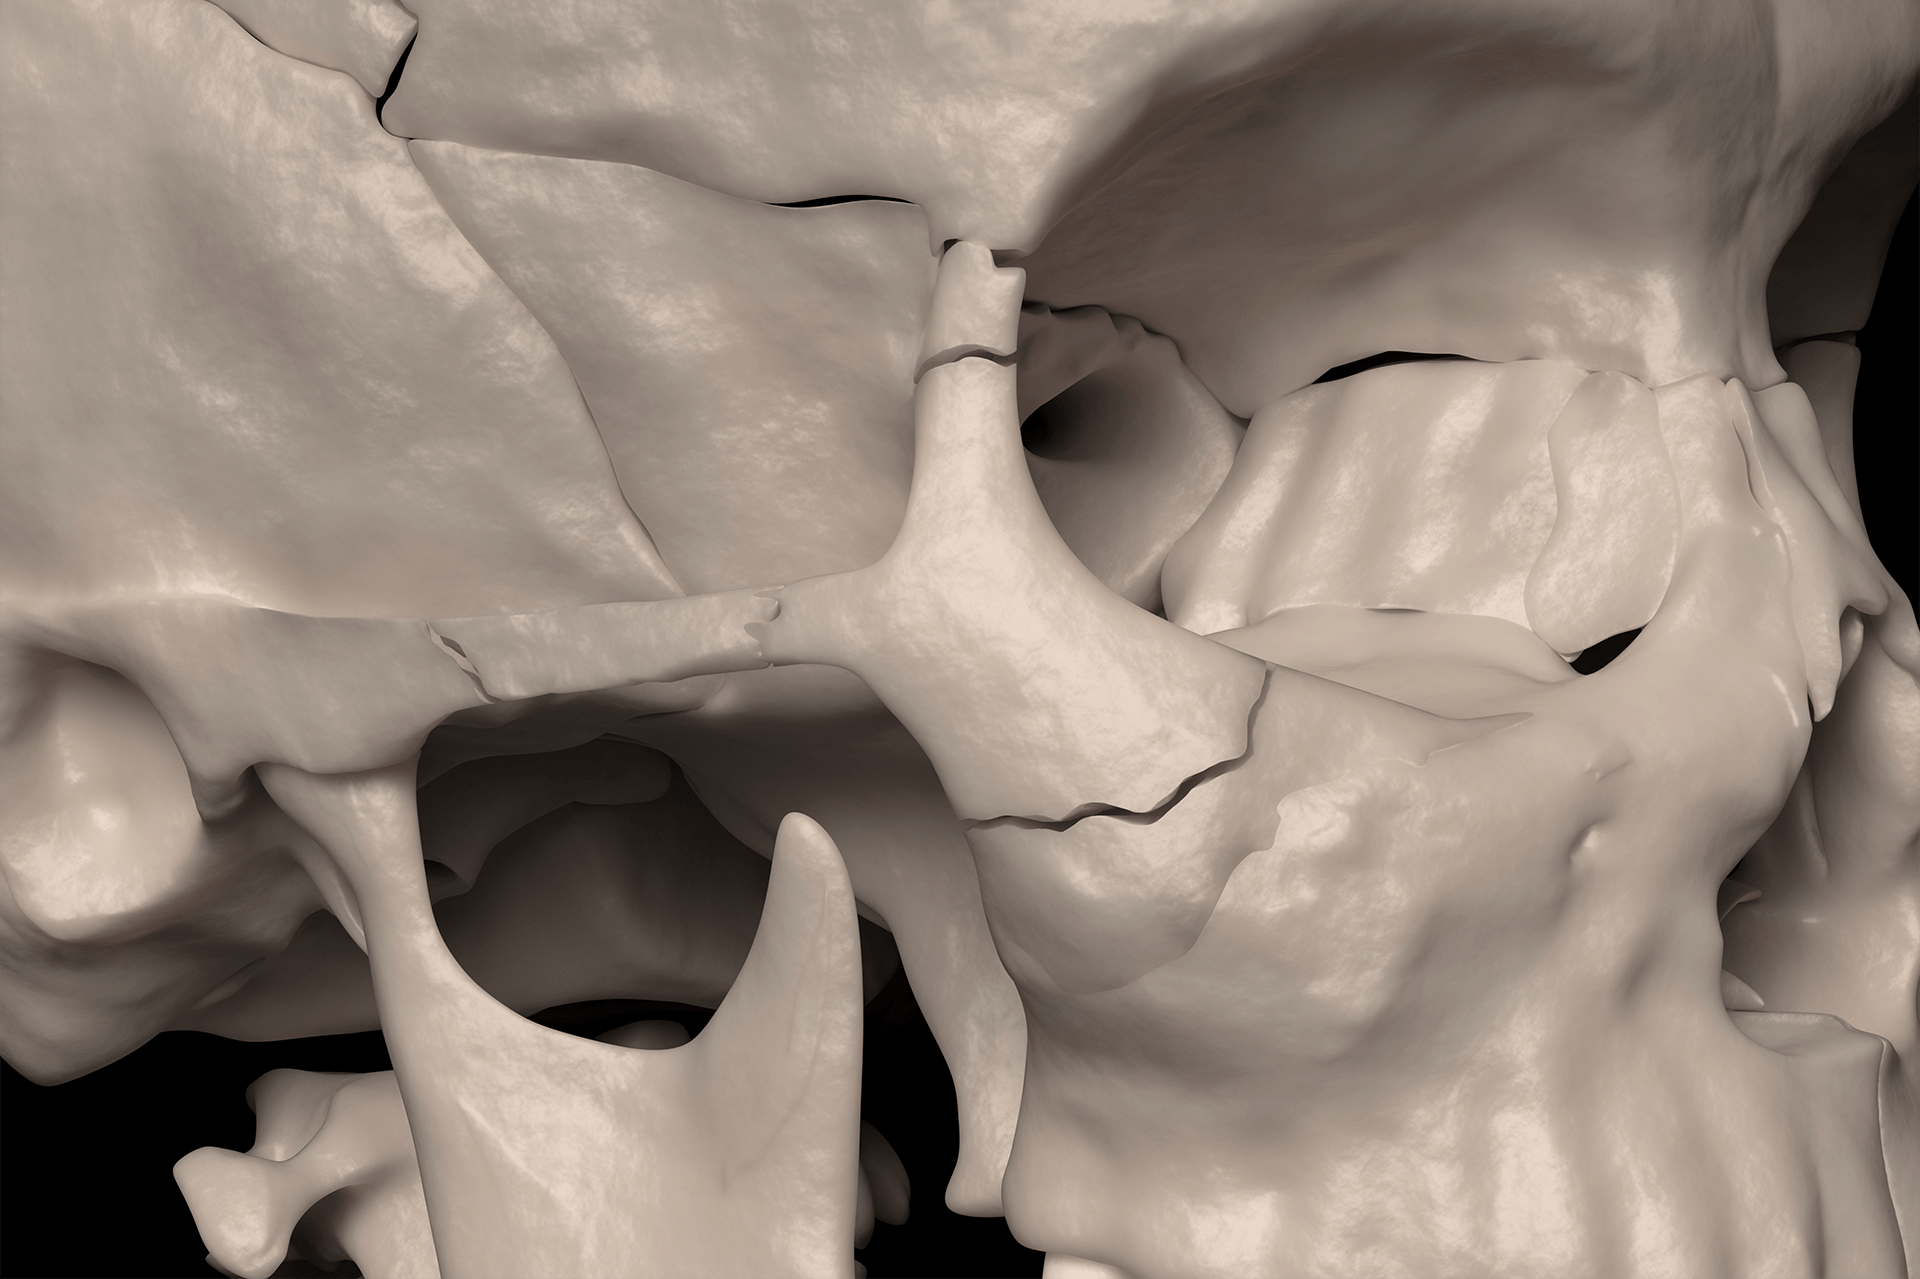

Complex facial fractures

Complex facial fractures 142 photos